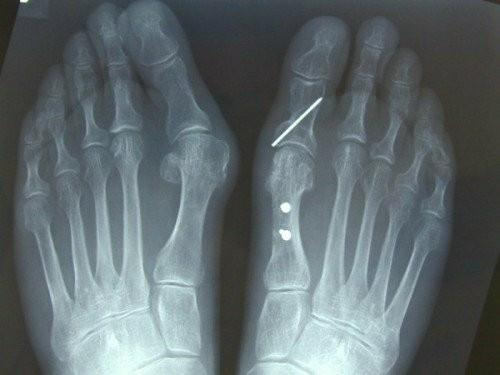

骨痛系列(三)------大脚趾骨痛

从脚趾通往脚腕的长骨(位于脚背皮肤之下;第二根脚趾的长骨痛最为多见